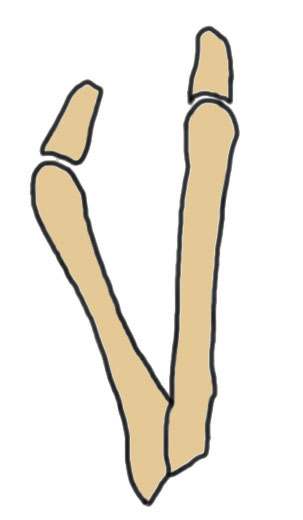

Coughlin Classification

| Type I | Type II | Type III |

|---|---|---|

| Prominent lateral condyle 5th metatarsal head | Lateral bowing of 5th metatarsal |

Increased 4/5 intermetatarsal angle Normal 5 degrees 5th metatarsal straight |

| Lateral condylectomy | Osteotomy | Osteotomy |

Lateral bowing of 5th metatarsal

Increased intermetarsal angle (IMA). Normal is 5 degrees